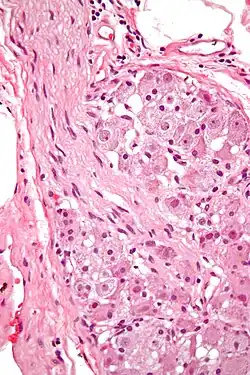

![]() Various forms of nerve cells.

During the late 1800s, early 1900s, Spanish Neuroscientist and Pathologist Santiago Ramón y Cajal proposed Neuron theory which basically introduced the idea that the Nervous system contained cells called the Neuron. The process he used was called Golgi staining of the vertebrate retina. Cajal was able to differentiate between different types of Ganglion cell based on dendritic morphology, cell body and dendritic tree size, and number of sub layers in which they arborize/stratification layers. Through this study, he discovered that the ganglion cell distribution amongst vertebrates were pretty similar minus the Rods and cones in the retinas.[3]